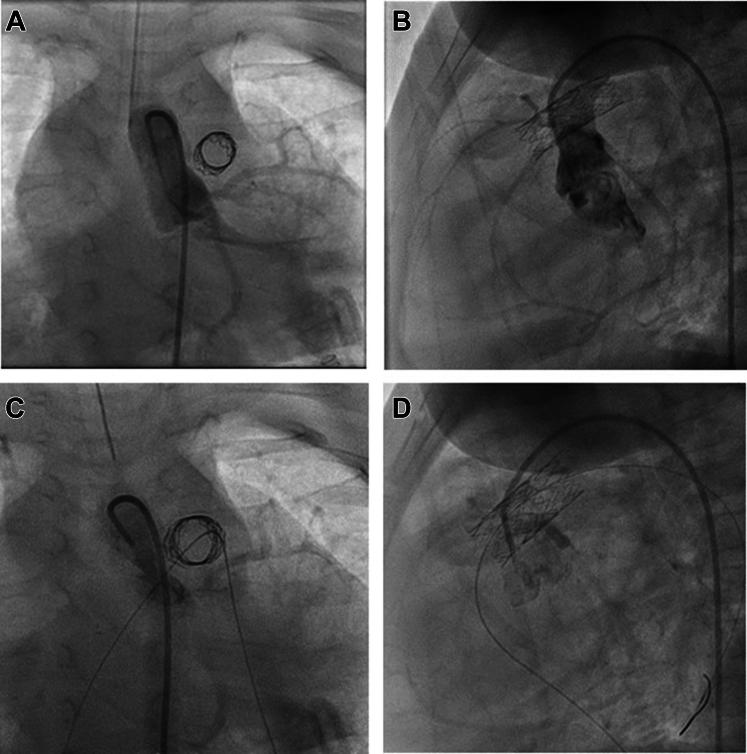

We describe an infant with a history of extreme prematurity, Noonan syndrome, hypertrophic cardiomyopathy, and severe valvular and supravalvular pulmonic stenosis who underwent right ventricular outflow tract stenting and mitogen-activated protein kinase kinase (MEK) inhibitor therapy.

我们描述了一名有极早早产史、努南综合征、肥厚型心肌病以及严重瓣膜和瓣膜上肺动脉狭窄病史的婴儿,该婴儿接受了右心室流出道支架置入术和丝裂原活化蛋白激酶激酶(MEK)抑制剂治疗。

This unique approach ultimately allowed for discharge home and postponement of surgical repair until 18 months of age.

这种独特的方法最终使患儿得以出院回家,并将手术修复推迟至18个月龄。